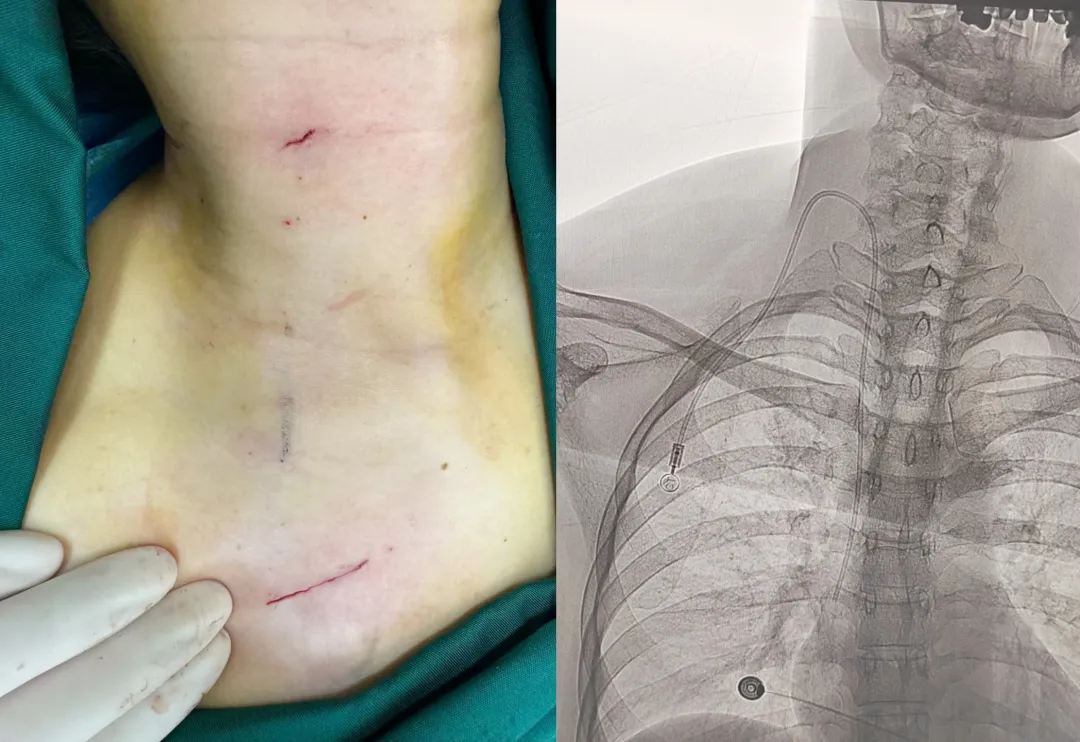

当日,李医生手术室团队紧密配合、通力协作,为患者进行了输液港植入手术。手术过程中,李医生在血管超声引导下行右侧颈内静脉穿刺,见回血后经穿刺针送入导丝至上腔静脉,退出穿刺针,沿导丝缓慢置入血管扩张鞘,拔除导丝,经扩张鞘送入硅胶导管至上腔静脉。在右侧锁骨下两横指处制作输液港囊袋,将体外导管用隧道针牵引至囊袋,修剪导管,将导管与注射座连接,术中实时采用DSA透视功能,确定输液港导管末端位置正确,最后将输液港放入囊袋,选择可吸收缝线,切口行皮内美容缝合,将疤痕降到最低程度。

手术顺利,仅用时40分钟,患者全程无任何不适,且术后也无需再次预约胸片评估导管末端位置,同时也无须担心术后拆线的困扰,避免了费时费力。这根导管将会陪伴病患数月甚至数年,整个化疗周期无须更换,且不影响日常生活,患者和家属都很满意。